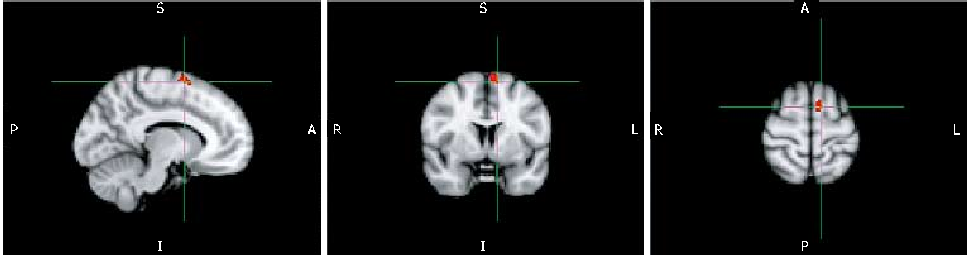

Figure 1

Cerebral magnetic resonance imaging in quiescent Crohn's disease patients with fatigue.

Figure 3